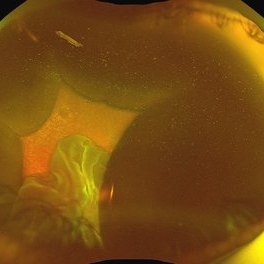

Suprachoroidal Hemorrhage

Suprachoroidal Hemorrhage

Aug 4 2025 by Anjana Mirajkar, MS Ophthalmology

A fundus photograph of a 56 year old female with a 360 degree suprachoroidal hemorrhage with a 360 degree crumpled retina during cataract surgery.

Photographer: Dr. Anjana Mirajkar- HV Desai eye hospital ,Pune

Imaging device: optos

Condition/keywords: giant retinal tear, suprachoroidal hemorrhage